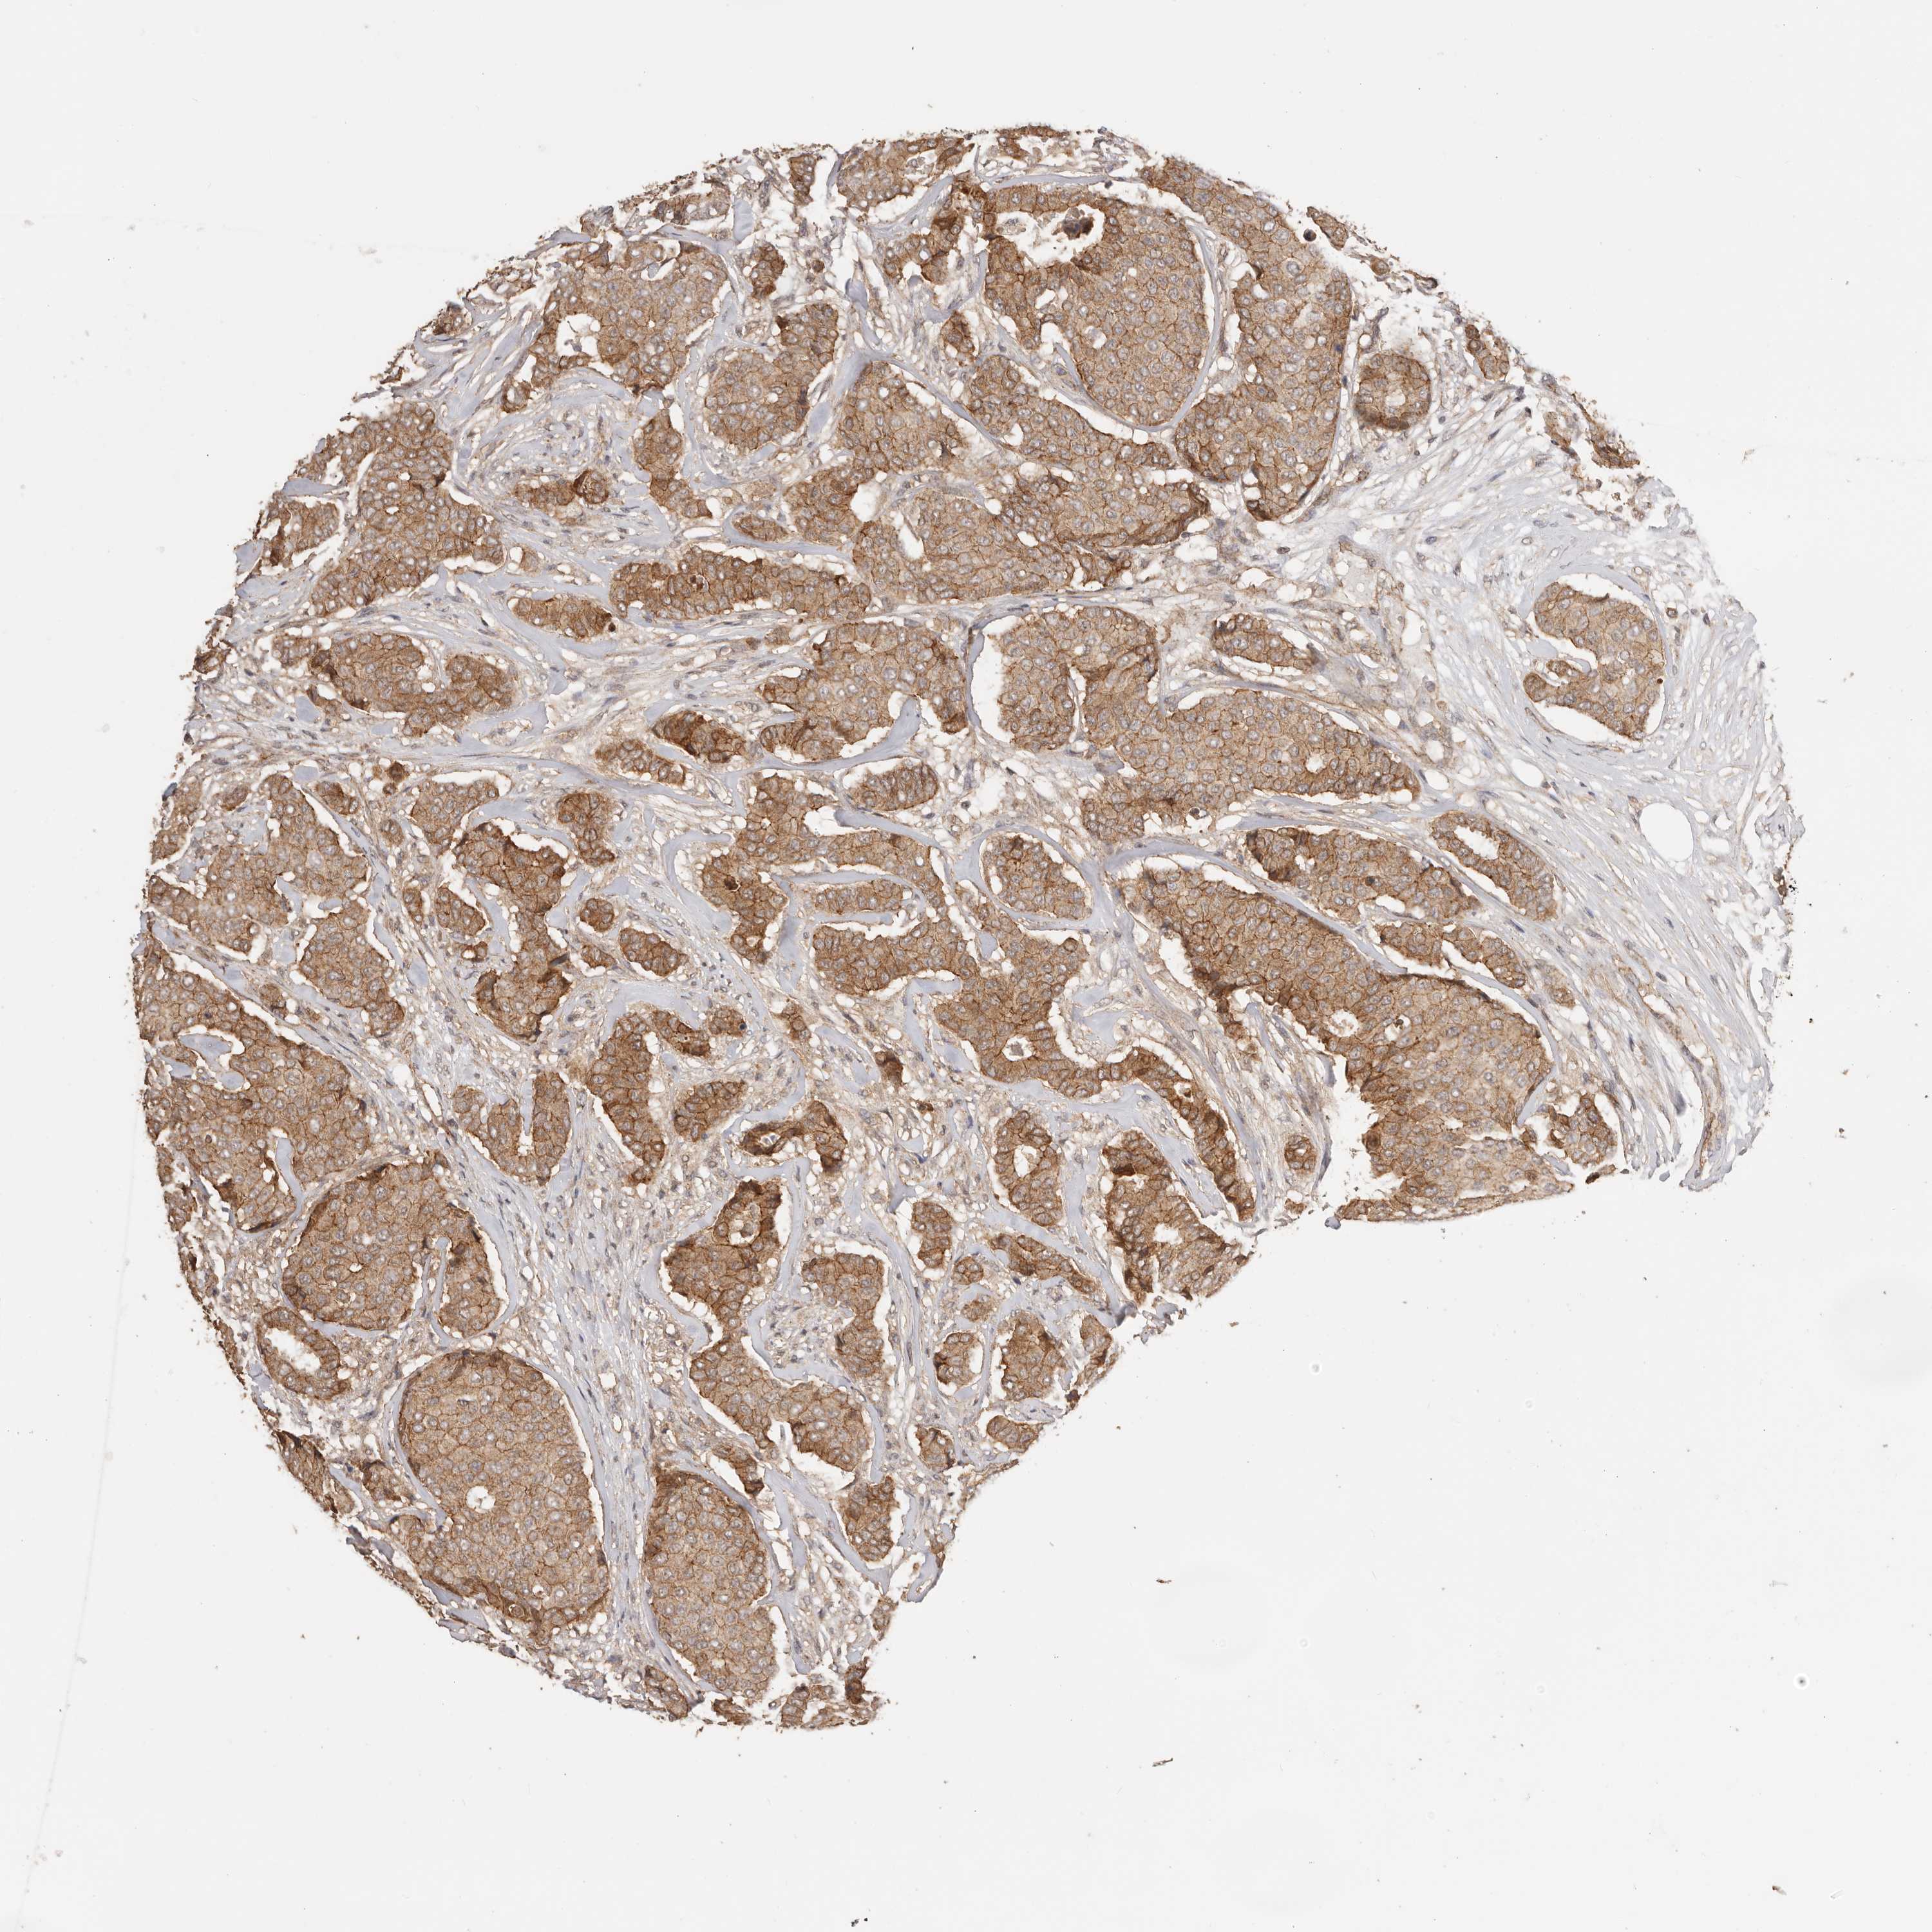

BRCA TCGA BRCA VALIDATION PROTEIN EXPRESSION

ANTIBODIES

AND

VALIDATION